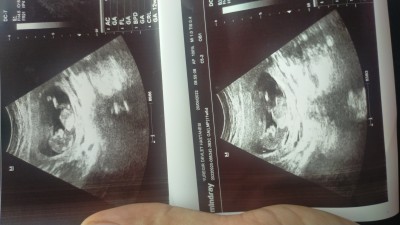

Bi bakar mısınız tahmin yapabilir misiniz başlık kabul etmiyor

Kızlar 12+1 tahmin edebilirmisiniz?